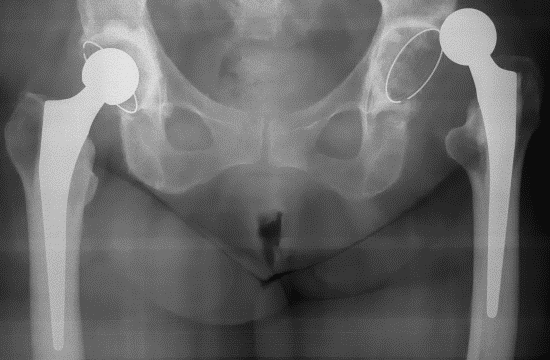

• Рентгеновские лучи. На фото хорошо видно расположение сустава и то, что он находится вне вертлужной впадины;